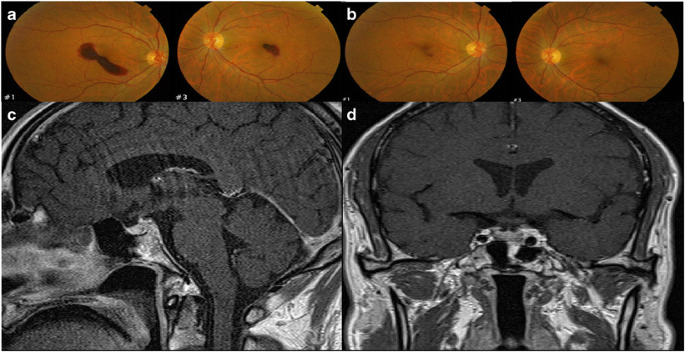

Plain chest and abdominal radiographs showed no abnormal findings. The patient showed reduced vision and bilateral conjunctival hemorrhage. Fundoscopy showed bilateral submacular hemorrhage, but visual field examination showed no abnormal findings (Fig. 2).

a In the patient diagnosed with HFRS, fundoscopy showed bilateral macular hemorrhage. b After 3 months of conservative treatment, fundoscopy showed an improved state. Contrast-enhanced sagittal T1-weighted image (c) and contrast-enhanced coronal T1-weighted image (d) show the size (vertical height 6.5 mm), shape, and density of the normal pituitary gland

Despite initially presenting with oliguria, his urine output began to increase on the second day to reach a 24-h urine output of 5–10 L after fluid therapy and preservative treatment. The diuretic stage persisted for > 3 weeks, with a daily urine output of > 10 L. The patient experienced thirst and general weakness. Serum cortisol, thyroid, and pituitary hormonal tests and a water deprivation test were performed, revealing a luteinizing hormone (LH) level of 0.31 mIU/mL (normal range, 1.5 to 9.3); follicle-stimulating hormone (FSH), 2.0 mIU/mL (normal range, 1.4 to 18.1); human growth hormone, 0.36 ng/mL (normal range, 0 to 1.0); and cortisol, 1.3μg/dL (normal range, 51.8 to 470.7); FSH and hGH were lower in the normal range; other hormone levels were lower than normal. A combined pituitary stimulation test was performed to assess hypopituitarism more accurately. Luteinizing hormone-releasing hormone (LHRH) 100 μg + thyrotropin-releasing hormone (TRH) 400 μg + regular insulin (RI) 7 U were injected intravenously. After stimulation, hormone levels did not reach the threshold range. Therefore, panhypopituitarism was diagnosed (Table 1) (Dennis et al. 2015). The patient was diagnosed with panhypopituitarism, and prednisone and thyroid hormone were administered. In the results of a water deprivation test, the urine osmolality increased from 196 to 250 mOsm/kg. After water deprivation, aqueous vasopressin (5 U) was injected intravenously. Urine osmolality was elevated by > 50% compared with baseline levels (250 to 385 mOsm/kg); thus, the patient was diagnosed with complete central diabetes insipidus (DI) (Table 2) (Goldman and Schafer 2016). Brain MRI approximately 1 month after admission showed normal vertical height of the pituitary (6.5 mm) with no abnormal contrasts or atrophy (Fig. 2). Desmopressin was administered and his 24-h urine output dropped to 3 L, with improvement in the symptoms of thirst and polyuria. The patient showed improvement with continued administration of prednisone, thyroid hormone, and desmopressin (Fig. 3).